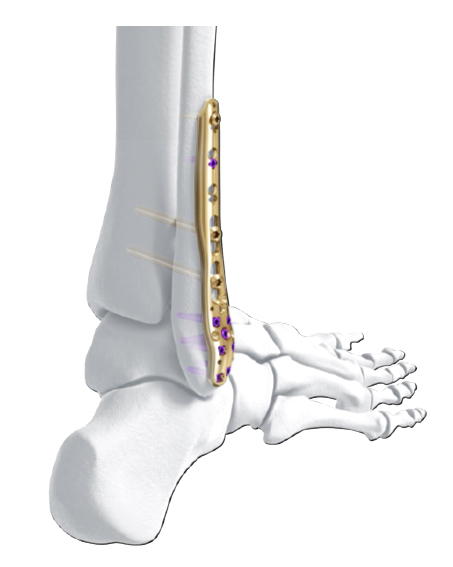

The Variable Angle LCP Ankle Trauma system also comprises a compression and distraction system, which is an important tool for reduction (i.e. bringing a fibula out to length) or compression of a fracture through the plate itself (Fig 9a-d). The forceps allow for final screw fixation after compression or distraction has been achieved.